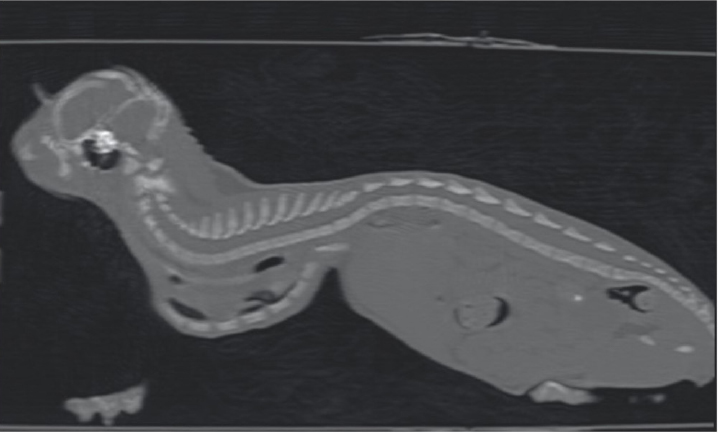

One month later, the kitten weighted 550 g and presented again for intermittent tachypnea, needing oxygen administration, and exercise intolerance. A preoperative CT was performed to evaluate the exact position of the intrathoracic structures and to assess safe corridors for the needle passage. CT was performed using a 20 slice TC scanner (Siemens® Somatom Sensation Open, Munich, Germany) with a 140 Kw and 150 mAs technique, in the awake patient, using a Plexiglas “mouse trap” (VetMouse trapTM) to restrain the animal. Only basal scans were obtained with 2 mm slice thickness, using 0.5 seconds rotation time. CT confirmed radiographic findings, adding more details (Fig. 3). Tomographic images revealed a complete dislocation of the heart into the left hemithorax, with complete atelectasis of the caudal portion of the cranial left lung lobe and partial atelectasis of the caudal left lobe near the hilum. The heart and the tracheal bifurcation were dislodged cranially compared to the normal anatomical position. The aortic arch was completely left-placed, together with the heart, but properly positioned at the level of the aortic hiatus. The caudal vena cava was dislocated to the left, resulting in a more central position, exactly interposed between the 12th vertebral body and the xiphoidal cartilage apex. The caudal vena cava and the aorta completely occupied the narrowed diaphragmatic portion of the thorax at the level of the xiphoid cartilage.

Fig. 3. Longitudinal reconstruction from CT scan. Notice the close relationship between the xiphoid process and the ventral aspect of the vertebral column.

Fig. 7. Transverse CT scan of the cat’s chest at the level of the xiphoid process, soft tissue window view (A), and bone window view (B).

The cat in this report was 3 months old and, based on the pectus severity index, had a severe pectus excavatum; therefore, an external splinting technique with a 3D-printed cast, customized on the base of CT images was chosen. CT scan was useful to better assess skeletal deformities, anomaly of the intrathoracic structures, and safe corridors for the needle passage. Moreover, CT was fundamental to design the splint. Five sutures were applied, the most caudal three being gradually pulled outward the concave part of the sternum and the other two directly ligated to the splint. The decision to surgically approach the seventh sternebra and xiphoid process to place the corresponding suture under direct vision was taken based on the result of the CT scan. CT images showed a close relationship between the seventh sternebra and the xiphoid process (Fig. 7), with the aorta and caudal vena cava occupying most of the thoracic space, making blind passage of the needle too risky. With this approach, the skeletal segment could be grasped and pulled ventrally, increasing the space for a secure passage of the needle. There were no surgical complications such as organ laceration or puncture, nor postoperative complications such as re-expansion pulmonary edema. The concern of the development of the re-expansion pulmonary edema, based on the sudden increase of the intrathoracic pressure due to the correction of the sternal concave deformity, lead the authors to the decision to gradually correct the sternal deformity. In this way, the increase in intrathoracic pressure and, therefore, lung re-expansion occurred little by little, reducing the risk for this complication. For these reasons, the sutures were gradually tightened during the first 2 weeks in response to the skeletal development of the kitten, and then kept in place for further 2 weeks to allow consolidation. The use of an electrician terminal block applied to the ventral part of the splint between the two rows of holes for the passage of the sutures perfectly fit this purpose. These locking clips allowed holding the sutures in position without the need to untie them each week.